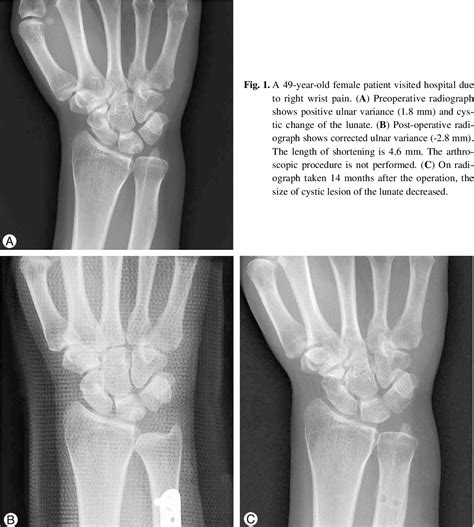

Imaging is equally vital. Standard X-rays, particularly those taken in a neutral position, help clinicians measure the ulnar variance. In more complex cases, an MRI is ordered to evaluate the extent of TFCC damage, cartilage wear on the lunate, or subchondral bone edema, which is the "bruising" of the bone caused by persistent impaction.

• Ulnar Shortening Osteotomy: A procedure where a small section of the ulna bone is removed, and the bone is fixed back together with a plate and screws to shorten it, effectively creating more space in the wrist.